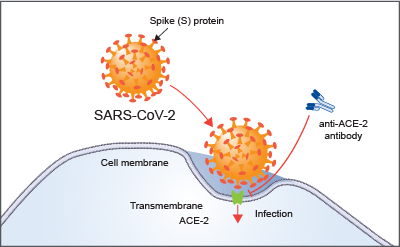

SARS-CoV-2 的刺突蛋白是病毒表面的糖蛋白,由两个主要功能结构域 S1(14-667 aa)和 S2(668-1255 aa)组成,分别介导与宿主细胞受体结合和膜融合。病毒的附着和进入宿主细胞取决于刺突蛋白的受体结合域(RBD:306-527aa)与特定细胞蛋白的相互作用。

研究表明,血管紧张素转化酶 2(ACE-2)和蛋白酶 TMPRSS2 分别是 SARS-CoV-2 进入宿主细胞所需的细胞受体和蛋白酶。靶向 ACE-2 的抗体(中和抗体 AF933,21 Citations),有望成为治疗新冠肺炎的有效方法之一。

蛋白酶 TMPRSS2 和/或 cathepsin L 在 S1-S2 连接处切割刺突蛋白,从而使病毒包膜与细胞膜融合,促使病毒 RNA 进入细胞。SARS-CoV-2 也可以被 furin 蛋白酶切割,其识别 S1-S2 连接处的四个氨基酸序列。除了在 S1-S2 连接处切割刺突蛋白外,细胞蛋白酶还可以剪切 S2 亚基,这对于刺突蛋白的激活和随后的膜融合至关重要。